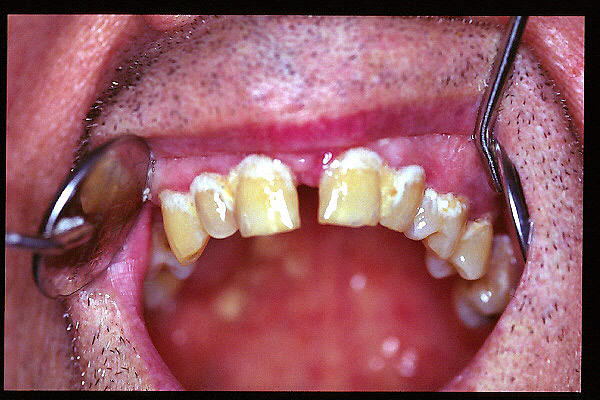

CM Desgaste por bruxismo, presencia de cálculo